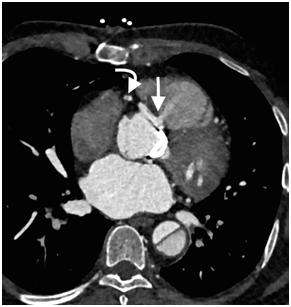

Cardiac computed tomography (CT) demonstrated patent left coronary arteries, a massive dissection flap extending from beyound the arortic graft to involve the descending aorta and a right coronary artery (RCA) dissection extending from the origin to the distal segment of RCA (Figure 4 & 5). The coronary dissection was not flow limiting and there was no evidence of obstructive coronary artery disease. The aorto-right ventricular fistula (ARV fistula) was detected by CT as a small defect four millimeters in size between the aorta and right ventricle (Figure 6).

Figure 6 CT Axial image demonstrates a small defect in the aortic root and contrast jet directed from the right coronary sinus towards the right ventricle (arrow). The RCA dissection is seen in the same image (curved arrow).